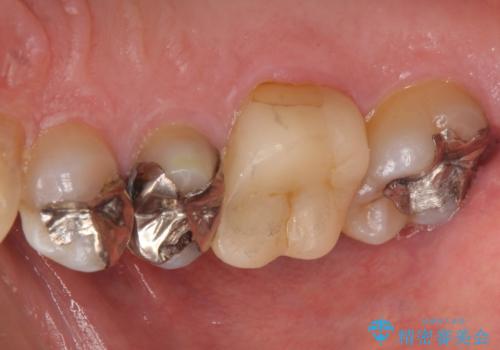

銀歯の下が虫歯 セラミックインレーに

- 銀歯の下が虫歯になっていたため、虫歯を取り、セラミックインレーで修復しました。

見るだけでは、わかりにくいのでしっかりレントゲンを診てもらえるような定期検診が大事です。